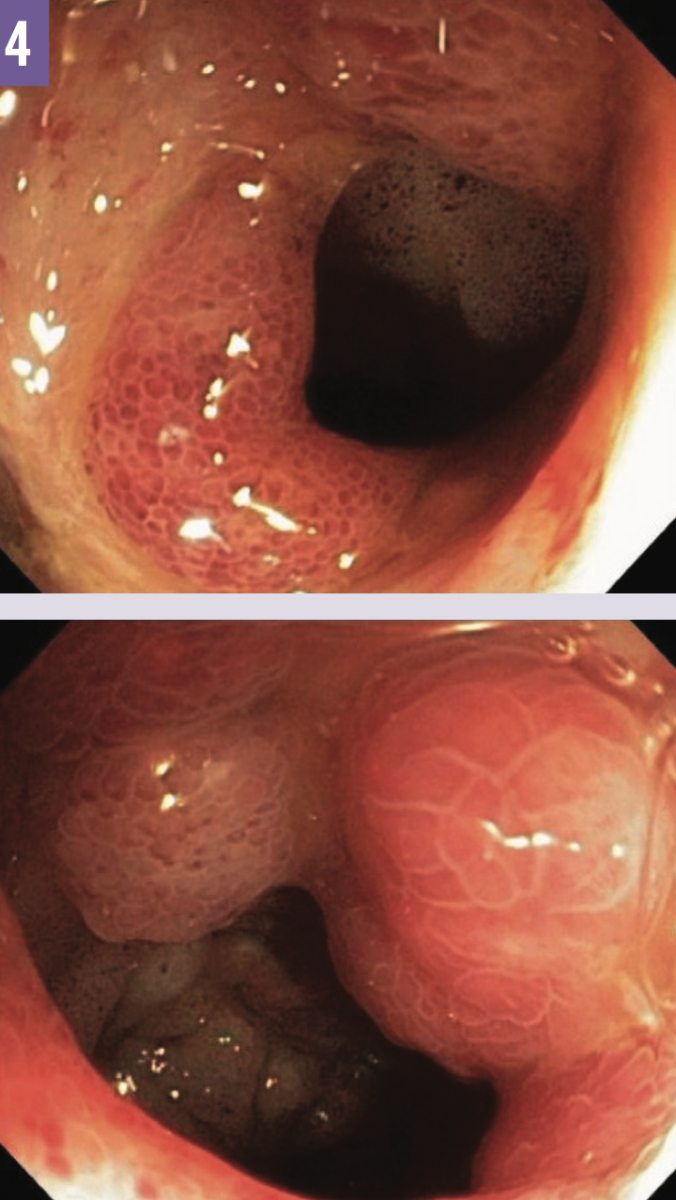

Results of QuantiFERON-TB Gold In-Tube tuberculosis (TB) antigen testing were indeterminate. Bronchoscopy was done, since the patient was unable to produce sputum; results of acid-fast bacillus testing of bronchial washings were +1 positive. Colonoscopy was performed, revealing erythema, edema, and friability at the ileocecal valve and at the terminal ileum (Figure 4); histopathology results of ileum biopsy showed multiple noncaseating granulomas (Figure 5) and Mycobacterium tuberculosis.

Figure 4: Colonoscopy revealed erythema, edema, and friability at the ileocecal valve (top) and at the terminal ileum (bottom).